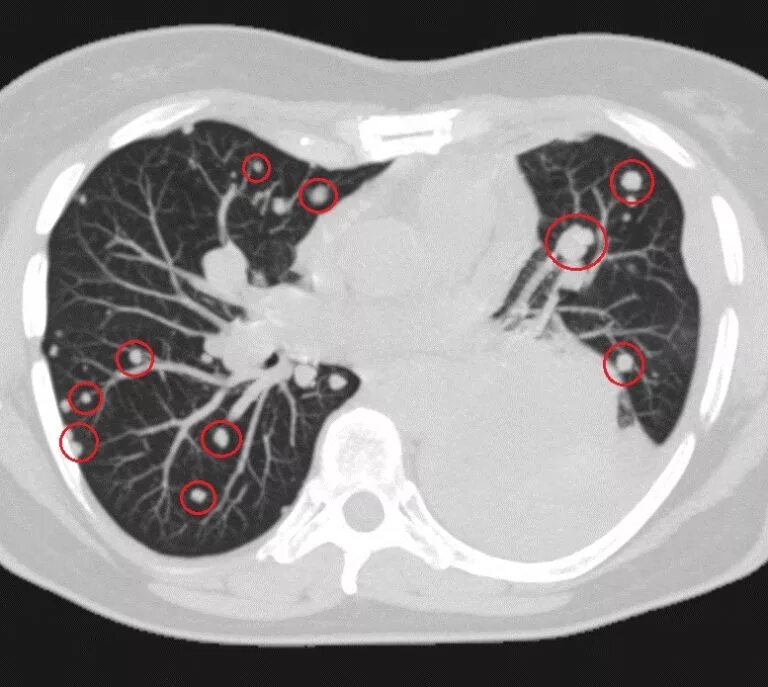

Как на кт выглядит рак